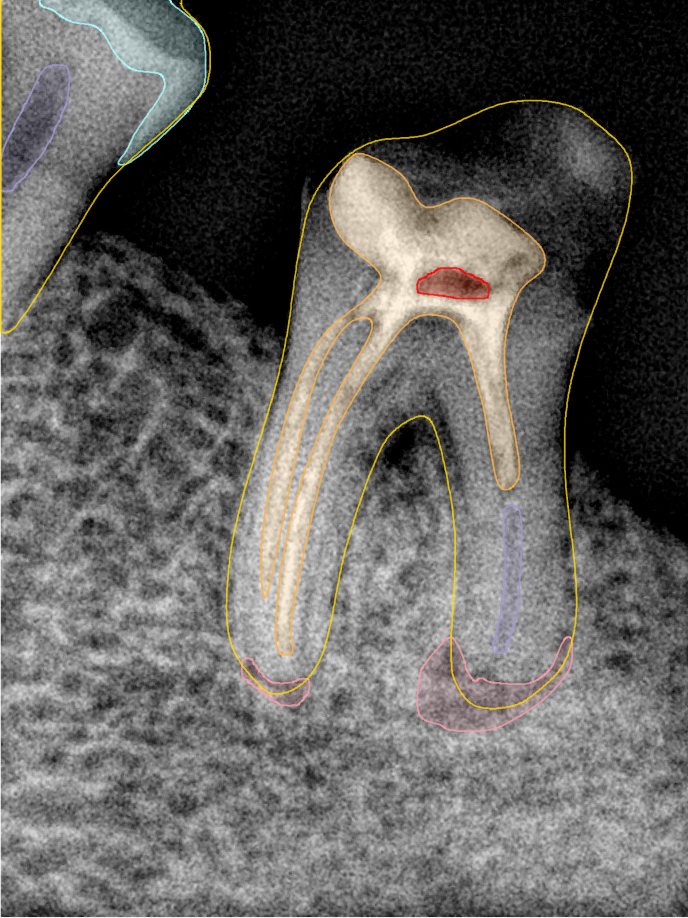

CR/DR 牙齿分割阶段记录

当前进展

- 完成了 CR/DR 牙齿相关分割训练

- 当前结果已经达到阶段预期,但仍有细节问题需要继续处理

相关测试

遇到的问题

- 训练过程中出现过 mask 下移问题

- 部分结果会出现 box 填充异常

- mask 边缘仍然有比较明显的锯齿感

参考

第二版算法问题测试